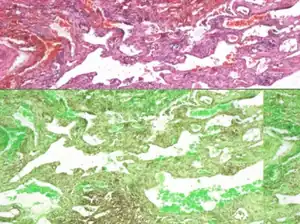

| Lung biopsy showing infiltration of lymphatic tissue. | |

Microscopic examination of biopsy specimens reveals an increase in both the size and number of thin walled lymphatic channels along with lymphatic spaces that are interconnecting and dilated, lined by a single attenuated layer of endothelial cells involving the dermis, subcutis, and possibly underlying fascia and skeletal muscle.[3] Additionally, Tazelaar, et al., described a pattern of histological features of lung specimens from nine patients in whom no extrathoracic lesions were identified, which they termed "diffuse pulmonary lymphangiomatosis" (DPL).[4]